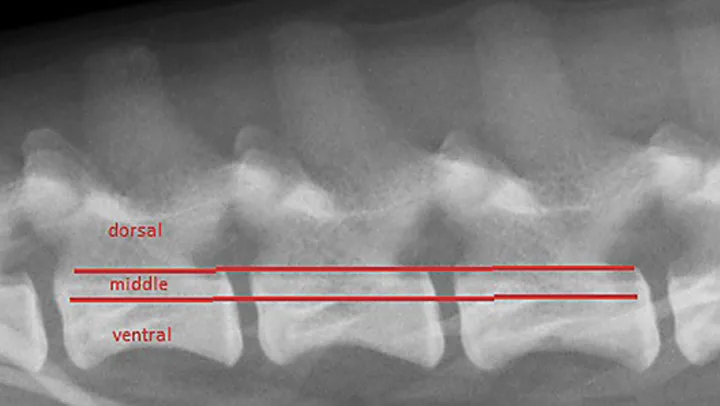

Determining whether a vertebral injury has led to vertebral column instability can be difficult. Vertebral luxations are inherently unstable, but vertebral fractures may or may not cause instability, depending on which structures are affected. One model for assessing potential instability divides the vertebral column into 3 compartments (Figure 3); if 2 of the 3 compartments are disrupted, the injury has likely compromised vertebral column stability, and additional corrective measures should be taken.

Figure 3

Three-compartment model of the vertebral column. The dorsal compartment includes structures dorsal to the line (ie, pedicles, laminae, articular processes, interarcuate ligaments, spinous processes). The middle compartment includes the dorsal aspect of the vertebral body, the intervertebral disk, and the dorsal longitudinal ligament. The ventral compartment includes structures ventral to the line (ie, the remainder of the vertebral body and intervertebral disk and the ventral longitudinal ligament).